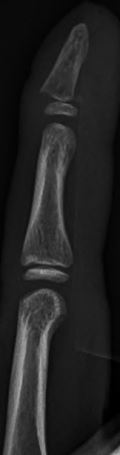

Middle or Proximal Phalanx Fractures

Shaft Fracture

Management: Reduction in ED if angulated or displaced.

Place in neutral hand splint. (Buddy taping may be ok for non-displaced fracture)

Phalangeal_image4